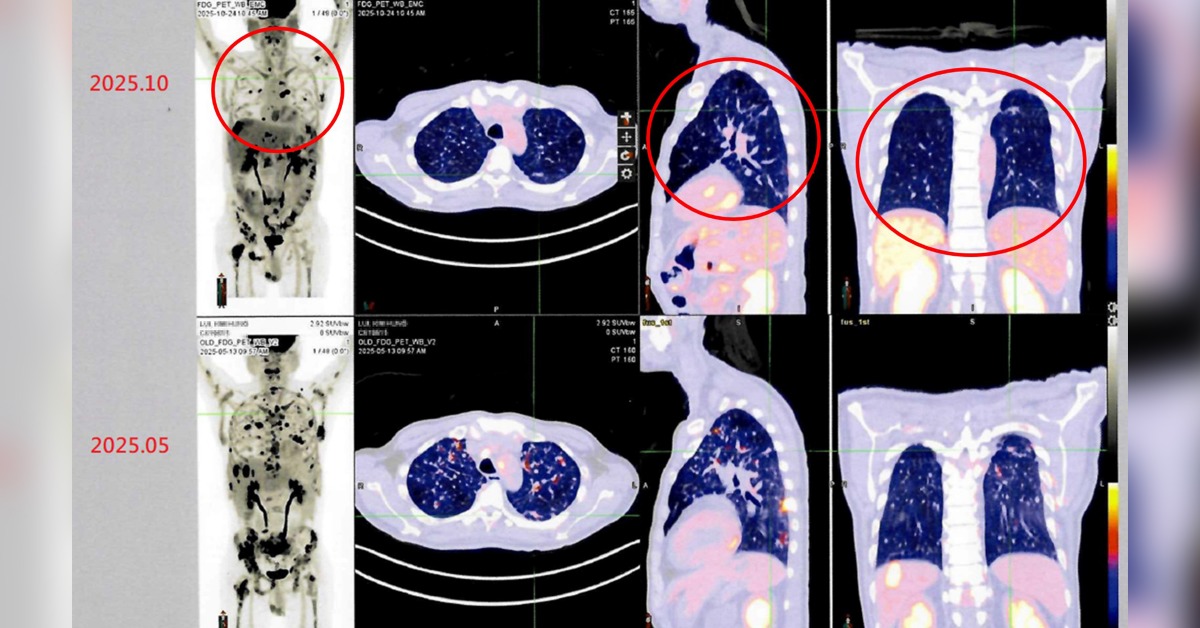

病人接受自體免疫細胞治療(DC-CIK)後,從治療前後影像資料對比(紅圈處),可發現癌細胞減少許多,顯示病情穩定 。(圖/衛生福利部雙和醫院提供)

衛生福利部雙和醫院有位來自香港的男性病患(50歲)。他於2024年在香港被診斷出罹患第四期肺癌,歷經多次傳統化療與標靶治療後,為尋求新的治療機會,他評估後決定來台灣進行自體免疫細胞治療(DC-CIK)。經過半年整合療程後,最新影像檢查顯示病情穩定,疼痛症狀明顯獲得緩解,體能與生活品質大幅提升。